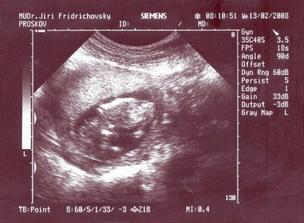

13.2. Mám fotečku z dalšího UTZ, hrášek má 12cm a je to už pěknej macek... 18.2. jdeme na krev na tripple testy (snad to bude vše v pořádku) a další kontrola 12.3.